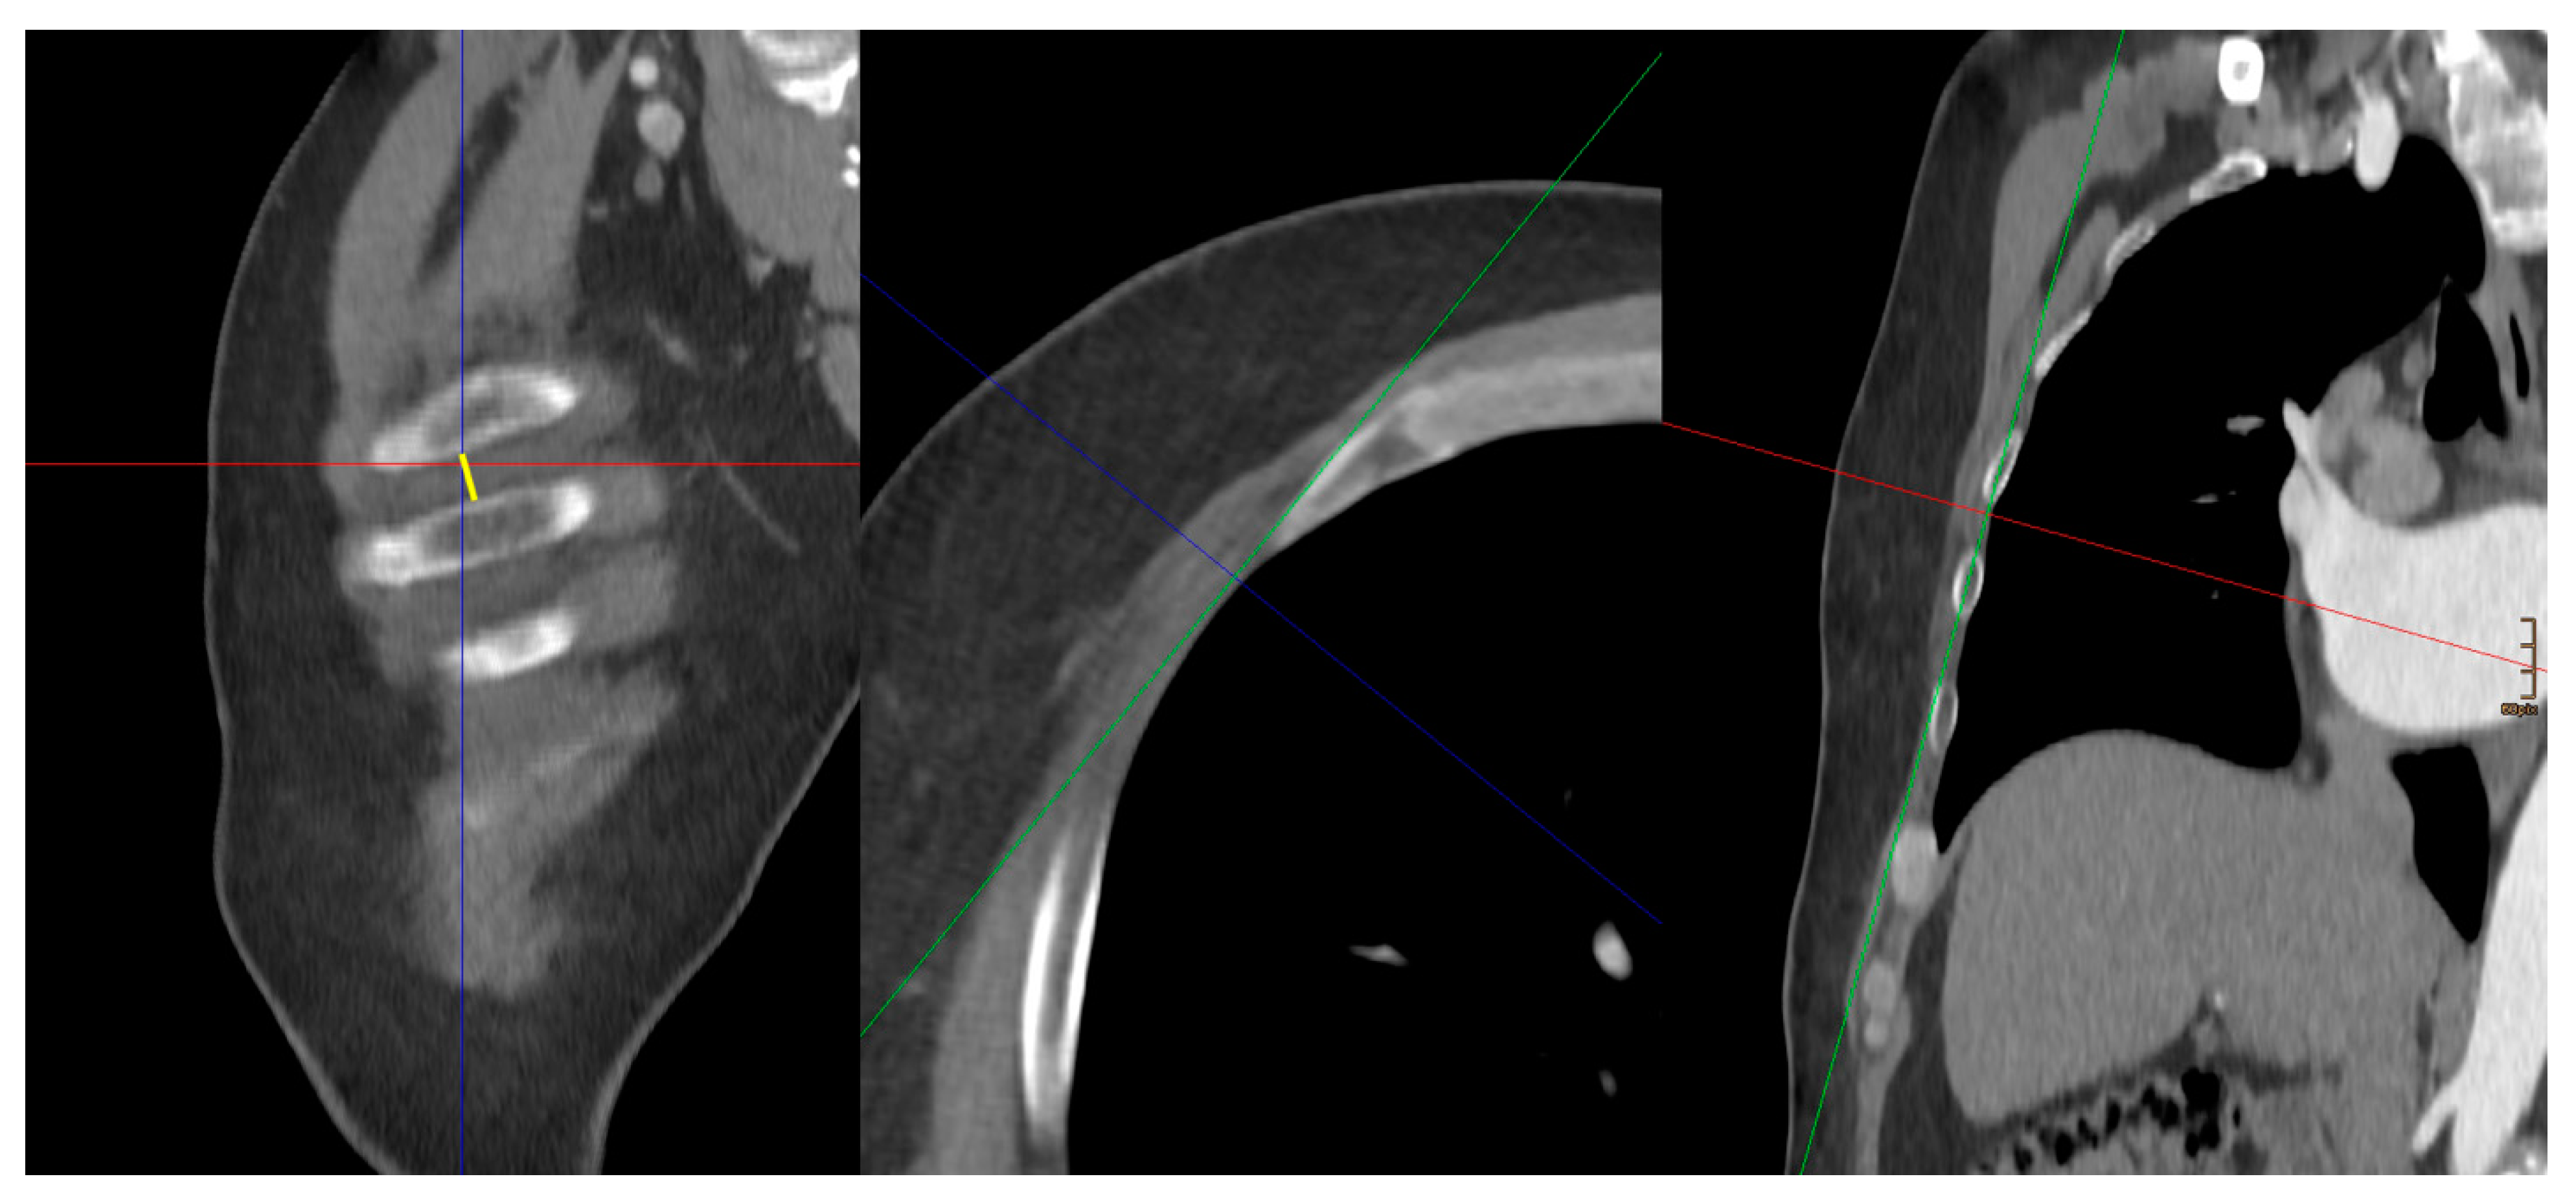

The following morphological parameter data were measured and collected retrospectively (Figure 1, Figure 2 and Figure 3):

DSS–Distance between the sternum and the spine: On an axial image, at the level of the midportion of the mitral valve.

DSM–Distance between the sternum and the anterior annulus (A2) of the mitral valve: On an axial image, at the level of the midportion of the mitral valve.

DSA–Distance between the sternum and aorta: On an axial image, just above the right atrial appendage.

DNM–Distance between the nipple and the anterior mitral anulus: From an axial image view, the distance between the nipple as the entering point of the thorax and the anterior mitral anulus was measured. In female patients, the expected entering point through the fourth intercostal space with the tissue above was taken.

DVM–Distance to the left between the vertical and the anterior mitral anulus (DVM): From an axial image view, at the level of the midportion of the mitral valve, the distance between the vertical line of the DSS measurement and the anterior mitral anulus was measured. This is a parameter reflecting how far left the mitral valve is located in the thorax.

AMH–Angle between the mitral valve and the horizontal: From an axial image view, the angle between the mitral valve and the horizontal was measured. The plain of the mitral valve was defined by the connection line between the anterior and posterior anulus at the midportion (corresponding to A2, P2 segment) of the valve.

ANM–Angle between the mitral plane and the line from the working port to the mitral valve: From an axial image view, the angle between the mitral plane and the line from the working port to the mitral valve was measured.

ICS–Width of the intercostal space:

In multiplanar reformatting (MPR), the width of the corresponding intercostal space just below the nipple reflecting the entry site was measured.

Figure 1. Measurements. DSS–Distance between the sternum and the spine: yellow. DSM–Distance between the sternum and the anterior annulus (A2) of the mitral valve: orange. DNM–Distance between the nipple and the anterior mitral anulus: green. DVM–Distance to the left between the vertical and the anterior mitral anulus (DVM): dark blue. AMH–Angle between the mitral valve and the horizontal: light blue. ANM–Angle between the mitral plane and the line from the working port to the mitral valve: magenta.